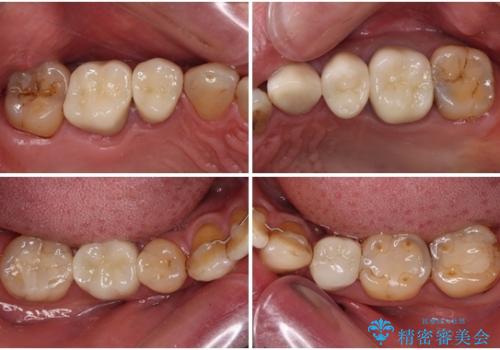

痛みは速やかに引き、銀歯や黒く変色したむし歯がセラミッククラウンで自然な色合いに仕上がり、患者様には大変満足していただきました。